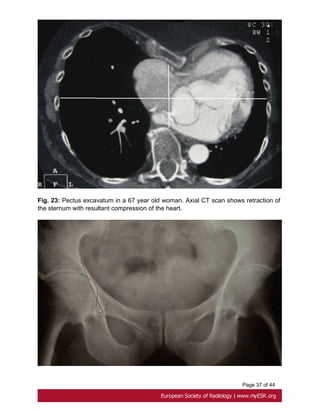

-Pectus excavatum is present in two thirds of patients with Marfan syndrome although

the incidence in general population is between 1 in 400 and 1 in 1000 births[34]. It results

from the displacement of the sternum and costosternal joints.

Pectus excavatum is considered severe if Haller index is above 3.25, which is the

ratio between the lateral distance of the chest wall at inner margins and the narrowest

anteroposterior distance between the vertebrae and sternum [35]. Fig. 23 on page 37

Fig. 23: Pectus excavatum in a 67 year old woman. Axial CT scan shows retraction of

the sternum with resultant compression of the heart.

Page 37 of44 Fig. 23: Pectus excavatum in a 67 year old woman. Axial CT scan shows retraction of the sternum with resultant compression of the heart.